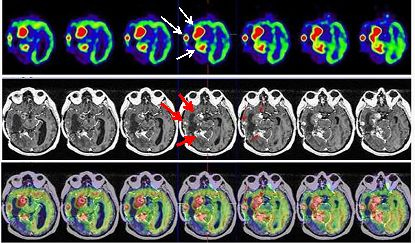

Tras los hallazgos del PET-RNM se procede a tratamiento radioterápico estereotáxico fraccionado, abarcando las lesiones captantes en el estudio PET-RNM, con fotones de 6 MV con técnica de arcoterapia conformada dinámica con un microcolimador multilámina, a razón de 2 Gy/día, 5 días a la semana hasta alcanzar una dosis total de 30 Gy. La RNM de control muestra cambios postratamiento en región mesial posterior del lóbulo temporal derecho, áreas de necrosis y hemorragia interna en vermis cerebeloso derecho. Al cabo de 5 meses, el paciente acude a Urgencias tras seguir tratamiento quimioterápico paliativo, presentando un cuadro de empeoramiento clínico de parálisis de III par óculo-motor derecho con caída del párpado superior y oftalmoplejia completa, parálisis del V par (trigémino) con anestesia de hemifacies derecha e importante alteración de la marcha por hemiparesia izquierda. La RNM informa persistencia tumoral en región mesial temporal derecha y en región posterior profunda, afectación tumoral en protuberancia y vermis cerebeloso. Se realiza estudio PET-RNM de reestadificación (figs. 5 y 6).